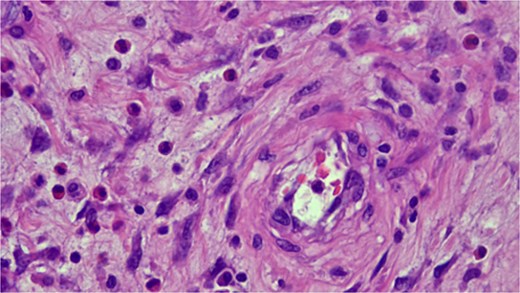

Imaging revealed an ileo-ileal intussusception with mild fat stranding but no evidence of bowel obstruction. This finding led to an ileal resection (17 cm) with primary anastomosis and lysis of adhesions. Pathology from the resected segment identified a benign spindle cell lesion consistent with an IFP, also known as Vanek’s tumor (Fig. 1).

Histopathologic examination showing spindle cells in a fibromyxoid stroma with a mixed inflammatory reaction, consistent with an IFP (Vanek’s tumor).

Microscopically, IFPs are composed of spindle-shaped, mononuclear cells arranged in a whorled or "onion skin" pattern around blood vessels and glands. The inflammatory infiltrate includes eosinophils, lymphocytes, macrophages, mast cells, and blood vessels, with a matrix of fine or collagen-rich fibrils. The classic gastric type, rich in eosinophils, has many spindle cells but minimal collagen, while the intestinal type is less cellular and more collagen-rich [16].